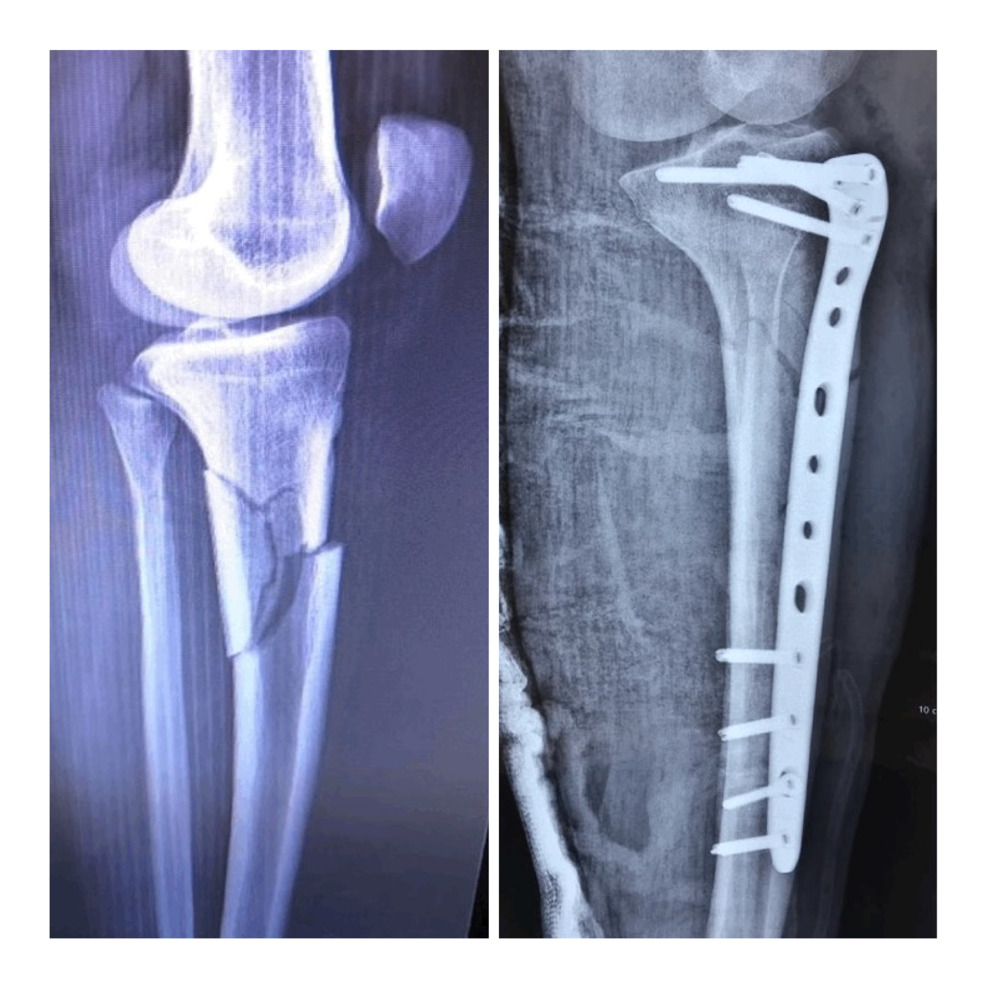

Our study included patients with fractures classified as 41-A2, 41-A3, 42B, and 42C according to the AO Foundation and Orthopedic Trauma Association classification (AO-OTA). Exclusion criteria included open tibial fractures, tibial fractures associated with neurovascular injury, and displaced intra-articular plateau fractures. All surgeries were performed by a single surgeon on a regular operating table. After obtaining informed consent and institutional ethical review committee approval, we included three patients with extra-articular comminuted proximal tibial fractures.

A limited anterolateral proximal tibial approach was then performed, followed by an anatomical proximal lateral tibial locking plate placement. Two proximal locking screws were placed to stabilize the plate and prevent rotation, followed by two distal cortical screws placed through a minimal incision under fluoroscopic guidance [Figure 1B]. After confirming appropriate reduction and alignment under fluoroscopy, additional locking screws were inserted [Figure 2].